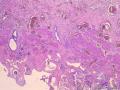

| 性别 | 女 | 年龄 | 44岁 | 临床诊断 | .胆总管下段结石并急性胆管炎 2.急性胆源性胰腺炎 3急性胆囊炎。 |

| 一般病史 | 上腹疼痛伴反复呕吐7天。血生化:ALT 268.0U/L,AST 157.0U/L,TBIL 64.3umol/L,DBIL 20.9umol/L,血糖:4.6mmol/L、血淀粉酶:3197.0u/L.腹部彩超示:胆总管上段结石并扩张。胰腺回声稍增粗声像。胆囊壁强回声实体物声像(考虑胆囊息肉)。 | ||||

| 标本名称 | 胆囊 | ||||

| 大体所见 | 灰绿、暗红色胆囊一枚,临床已局部剖开,大小:10x1-3.5x1.2cm。颈管开口直径0.4cm。囊内见胆汁,未见结石,近胆囊底部见长径0.1-0.4cm灰黄色息肉2枚,壁厚0.3-0.5cm,粘膜面粗糙似草莓状。 | ||||